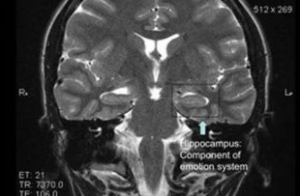

Dr. Souhel Najjar hatte Susannah gebeten, eine einfache Uhr zu zeichnen. Die Zeichnung einer runden Figur und der Schreibnummern entlang des Randes war eine einfache Aufgabe, um zu erreichen. Aber was um Susannahs Wiedergabe von einer Uhr war, war, dass ihre Uhr alle Zahlen auf der rechten Seite seines Gesichts zeigte. Es war ein klarer Indikator für Hirnschäden.

Die Diagnose von Dr. Najjar stellte sich schließlich als der richtige für Susannahs, das er selbst handelt. Er diagnostizierte sie mit Anti-NMDA-Rezeptor-Enzephalitis, einer Bedingung, die dazu führt, dass die Antikörper des Immunsystems das Gehirn angreifen.